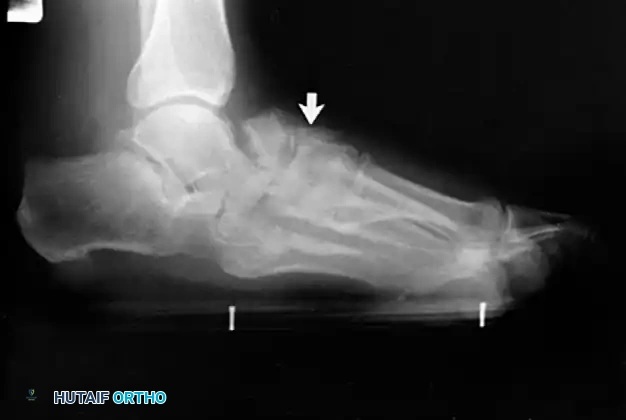

Clinical Pearl: The loss of the medial longitudinal arch can occur at the talonavicular, navicular-cuneiform, or cuneiform-metatarsal articulations. A weight-bearing lateral radiograph may initially show no bony collapse, appearing identical to the asymptomatic contralateral foot, even in the presence of obvious clinical pes planus.

- Clinical Findings: Loss of PTT function resulting in a flexible flatfoot deformity (hindfoot valgus, midfoot abduction). Mild lateral sinus tarsi pain may begin to manifest.

- Radiography: Degenerative arthritic changes are visible in the subtalar and/or talonavicular joints.

Associated Surgical & Radiographic Imaging